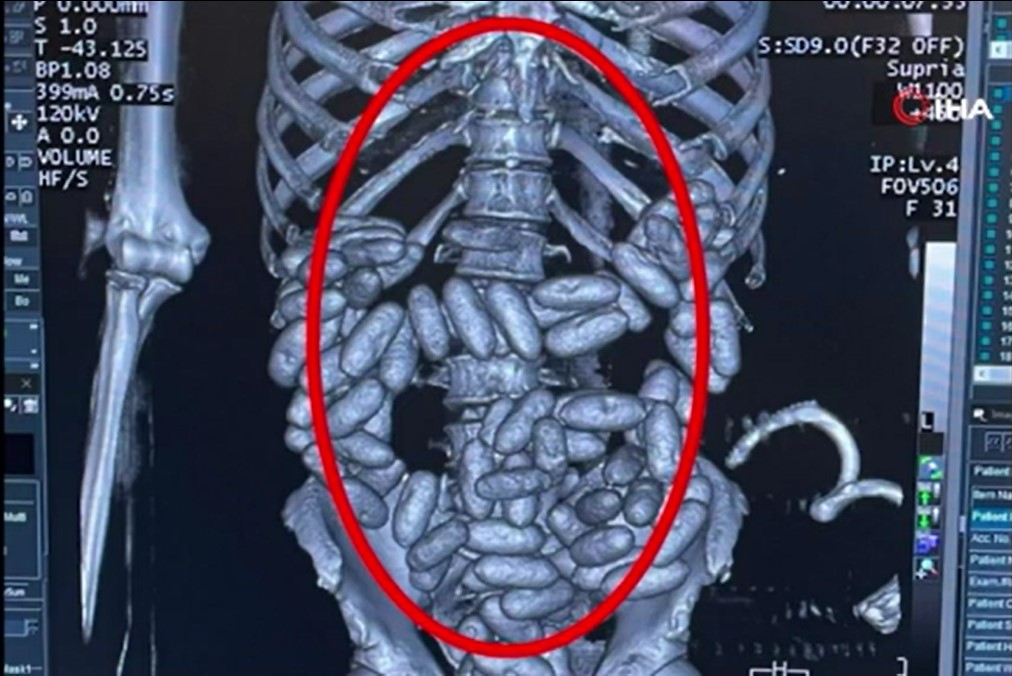

İstanbul Havalimanı'nda, Afrika kökenli bir yolcunun midesinde 2 kiloya yakın 96 kapsül kokain tespit edildi. Uyuşturucu kuryesi’ olduğu değerlendirilen yolcu, tutuklandı.

Şüpheli tavırları dikkat çeken B.E.O.'nun midesinde uyuşturucu olabileceği ihtimali üzerine hastaneye götürüldü. Götürüldüğü hastanede yapılan incelemede B.E.O.'nun sindirim sisteminde 96 kapsül içinde 1 kilo 844 gram kokain tespit edildi.